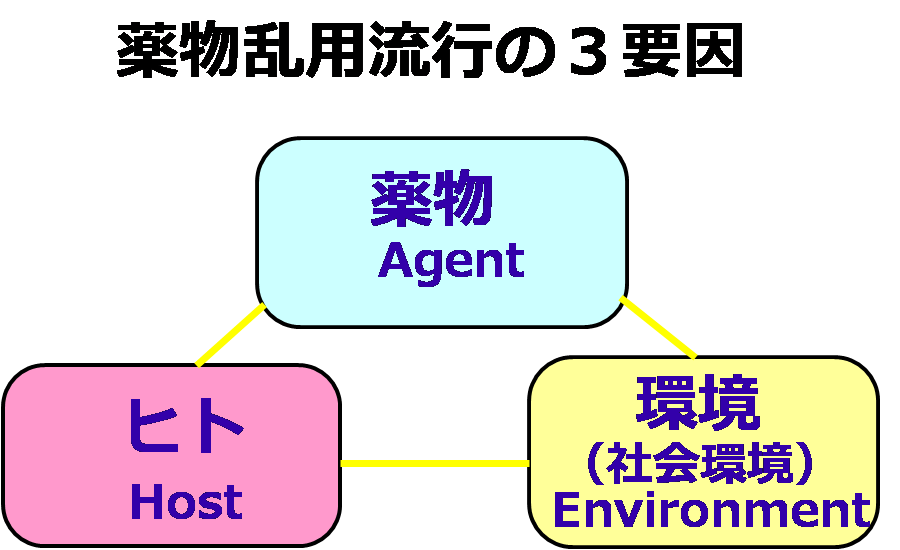

薬物乱用防止教育 q a 1 薬物乱用の基礎知識について

薬物乱用の科学

薬物乱用防止教育 q a 1 薬物乱用の基礎知識について